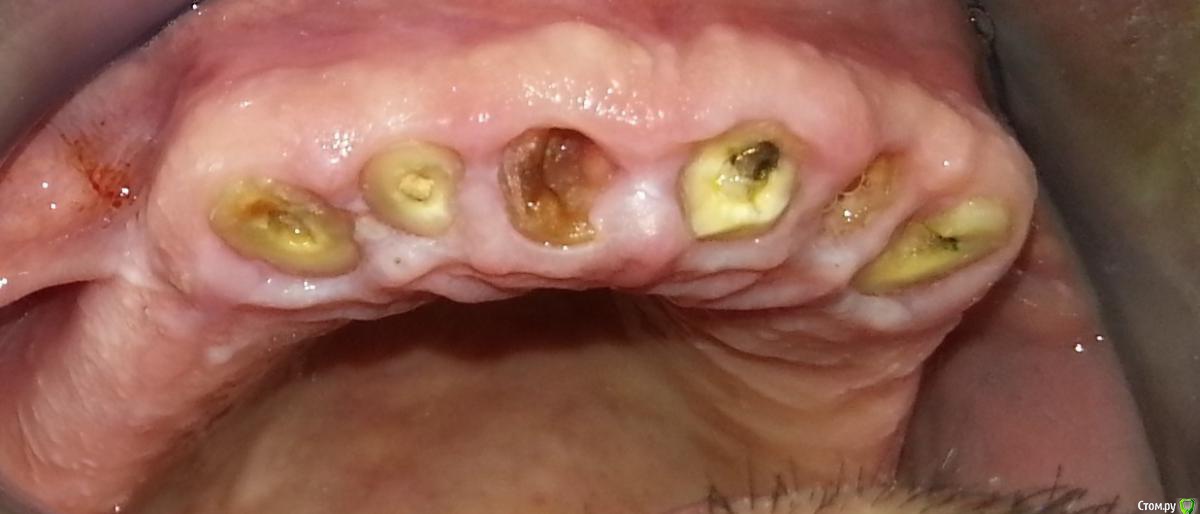

Nitrino1 Опубликовано 6 февраля, 2017 Поделиться Опубликовано 6 февраля, 2017 (изменено) Здравия желаю коллеги) Нужен совет опытных коллег, так как сам еще мало имею опыта в таких работах) Из анамнеза, был фронт мк, сначала расцементировка с одной стороны, и далее сломались зубы как видно на фотках. Хочет сохранить фронт своими зубами. Я посмотрел, как мне показалось реально вырулить если создать феррул в 2 мм. А после клыков уже имплантами восстаналивать. На данный момент перелечиваю 13й, попытался создать феррул в 2мм, на фотке можете увидеть. Как вы считаете, иду к успеху или к провалу? Что посоветуете?Вопросы:1. Беспокоит ситуация с 23им зубом, точнее с его апроксималкой (смотри ОПТГ), как поступить? Есть шанс сохранить зуб?2. Если получится сделать мост с 13-го зуба по 23-й зуб, тогда как поступить? Сделать вкладки , далее мк. А потом уже переходить к имплантам? Просто до завершения лечения на имплантах, пройдет 4-5 месяцев, за это время он не выбьет фронт нижними зубами? В Розинштиле написано что при восстановлении всей челюсти, лучше начать с фронта, создать эстетику на планируемую высоту а далее уже задние зубы под эту высоту...Буду рад любым дельным советам и рекомендациям)П.С. удалить сразу, самый простой способ)) П.П.С Последняя фотка, это после удлинения 13зуба) тоже буду рад замечаниям Изменено 6 февраля, 2017 пользователем Nitrino1 Ссылка на комментарий

Nitrino1 Опубликовано 7 февраля, 2017 Автор Поделиться Опубликовано 7 февраля, 2017 (изменено) chervoncevdaniilНет) Сначала бором прошелся по кругу, создал феррул 2 мм, потом коагулировал) Не правильный подход да? Где можно прочитать про правильное хирургическое удлинение и его тактику? Изменено 7 февраля, 2017 пользователем Nitrino1 Ссылка на комментарий

chervoncevdaniil Опубликовано 7 февраля, 2017 Поделиться Опубликовано 7 февраля, 2017 (изменено) chervoncevdaniilНет) Сначала бором прошелся по кругу, создал феррул 2 мм, потом коагулировал) Не правильный подход да? Где можно прочитать про правильное хирургическое удлинение и его тактику?Это не хирургическое удлинение,может феррул вы конечно и получите таким образом,но ценой жесткого нарушения биологической ширины со всеми вытекающими последствиями.Есть курс Марии Приямпольской или,как вам советовали,Анастасия Смолякову(она кстати тут на форуме есть),а где толково почитать не могу вам сказать Изменено 7 февраля, 2017 пользователем chervoncevdaniil Ссылка на комментарий